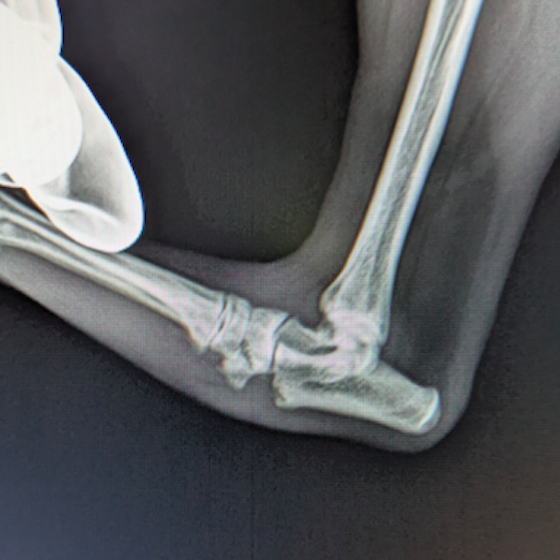

症例:トイプードル 9カ月齢

3ヵ月前より左前肢の跛行が認められるとのことで、来院されました。整形外科学的検査において、患肢の肘関節・肩関節重度の伸展制限が認められました。Xray検査において、左肩関節の内方脱臼、および肩甲骨関節窩の低形成と上腕骨頭の変形が認められました。

数か月に及ぶ慢性脱臼のため、関節面の低形成・摩耗のため整復手術による適切な再建は困難と判断し、切除関節形成術を実施しました。

術後3週間頃より、負重状態、歩行が改善しました。

切除関節形成術は、疼痛を引き起こす関節面を除去し、線維性偽関節の形成により患肢の機能改善を促す救済的手術です。術後のリハビリテーションの実施により、関節の可動域や患肢の筋肉量は改善され、生活の質は向上します。また本症例のように、慢性脱臼だけでなく、重度の骨関節炎症例にも実施することがあります。